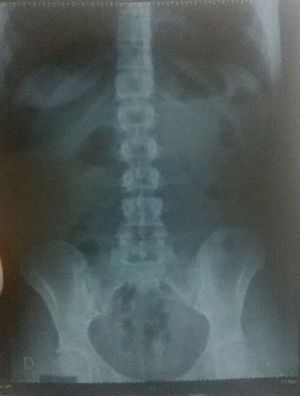

Whats wrong in this xray?

Sacroilitis with disc fusion.. Appears to be Ankylosing Spondylitis. Kindly provide the answer.